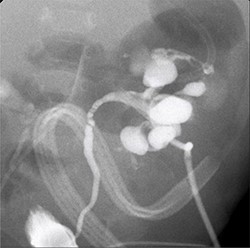

A 34-week preterm male infant was delivered by cesarean section due to fetal distress. He was admitted to the neonatal intensive care unit (NICU) due to neonatal sepsis and mild acute respiratory distress syndrome. He received gentamicin and amikacin for a week despite his hemoculture, sputum culture and urine culture revealing no growth. His clinical condition improved following treatment. Twenty-one days later he developed feeding intolerance, oliguria, a history of non-foul-smelling diarrhea, fever and alteration of consciousness. A physical examination found a body temperature 39.3°C, tachycardia and tachypnea. Laboratory examinations showed hyponatremia (Na 119 mEq/L), hyperkalemia (K 10.5 mEq/L), metabolic acidosis (HCO3 11 mEq/L) and azotemia (BUN 31.6 mg/dL) with acute kidney injury (Cr 5.1 mg/dL). The urinalysis revealed pyuria and yeast cells. Urine and hemoculture demonstrated C. albicans. The patient was transferred to the Pediatric Intensive Care Unit, where ultrasonography demonstrated a dilated renal pelvis and calyx in both kidneys and bilateral echoic lesions with central hyperechoicity, suggestive of fungal bezoars (Fig. 1) and a large amount of ascites. He was given intravenous fluconazole, normal saline boluses, potassium correction, sodium bicarbonate boluses and ultrasound-guided ascites aspiration was performed. After resuscitation and initial treatment, his serum creatinine decreased to 1.22 mg/dL and his blood culture was negative, however, urine culture continued to show the presence of C. albicans. Re-imaging showed bilateral complicated perinephric fluid collections and a large number of intra-abdominal fluid collections. The patient underwent a bilateral percutaneous nephrostomy. An antegrade pyelography found a filling defect in the bilateral pelvocalyceal system with contrast extravasation at the upper and lower poles of the left kidney (Figs 2 and 3), following which his creatine improved to 0.37 g/dL. After that, the patient underwent a left pyelotomy (flank incision) with bezoar removal and PCN replacement with a left double J stent. Two weeks later, we performed an open right pyelotomy and double J stent insertion via a flank incision. After the operation, his symptoms improved and his creatinine decreased to 0.27 mg/dL. Tissue pathology from the renal pelvis revealed fungal balls consisting of Candida spp. (Fig. 4). After 167 days of admission, he was discharged from the hospital with serum creatinine of 0.30 mg/dL.

Antegrade pyelography; filling defect in the left kidney and contrast extravasation at the upper and lower pole.